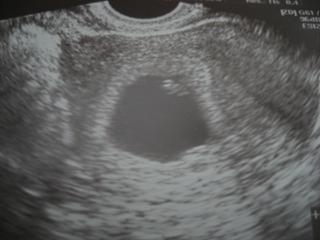

ahojky kocky, bola som dnes po prvy krat odkedy sme "cakatelia" u lekara.. urobil mi UTZ, poskusal brusko, kukol dnu a pogratuloval mi 😀

fazulka vyzera dobre, zdravo, srdiecko nam bilo o 106!

aj nam ju zmeral, ma 0,68 cm 😉 trosku sa nam posunul termin, bo podla UTZ mame nejaky 6tt + 4 dni... aj fotecku sme dostali, potom ju sem supnem... a o dva tyzdne sa mame prist znovu ukazat, ak bude vsetko tak ako ma, tak dostaneme aj tehu preukaz 😀 uz aby to bolo..........